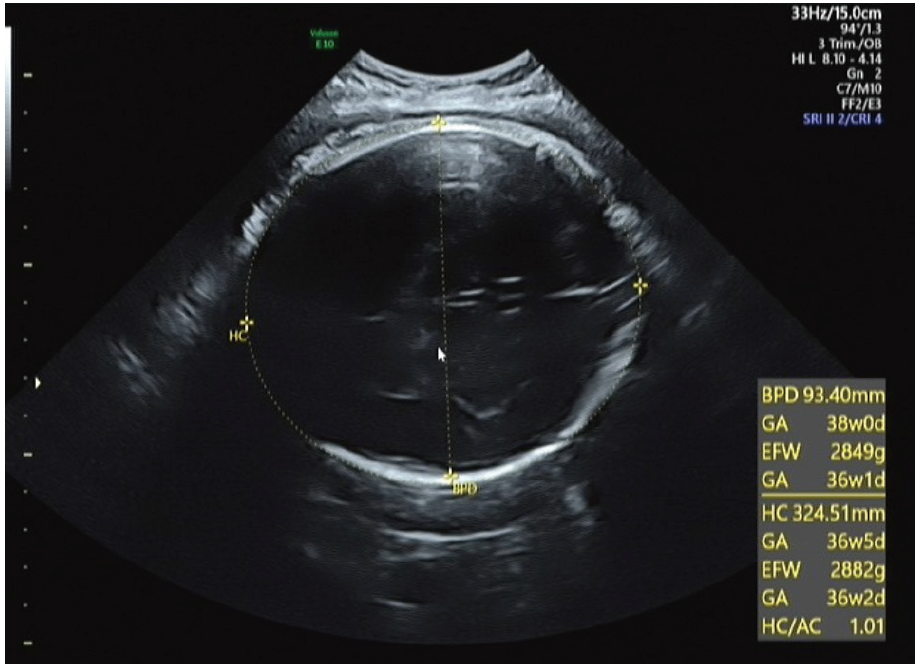

入院后采用广州莲印医疗科技有限公司wEye6产时超声系统在进行骨盆评估时同步完成,探头型号5C2AN,频率3~5 MHz。产妇测量时排空膀胱,采取仰卧位,双腿屈曲。将探头表面横向放置于产妇外阴,轻轻分开阴唇,获得盆底矢状面图。此时,耻骨联合和尿道位于视图前方,肛门位于后方。取耻骨联合下缘中点作为参考点,旋转轴面直到正中矢状面出现。图像中可观察到耻骨降支的全长,测量其夹角,见图1

图1 SPA的超声测量图像

Figure 1 Ultrasound assessment image of SPA